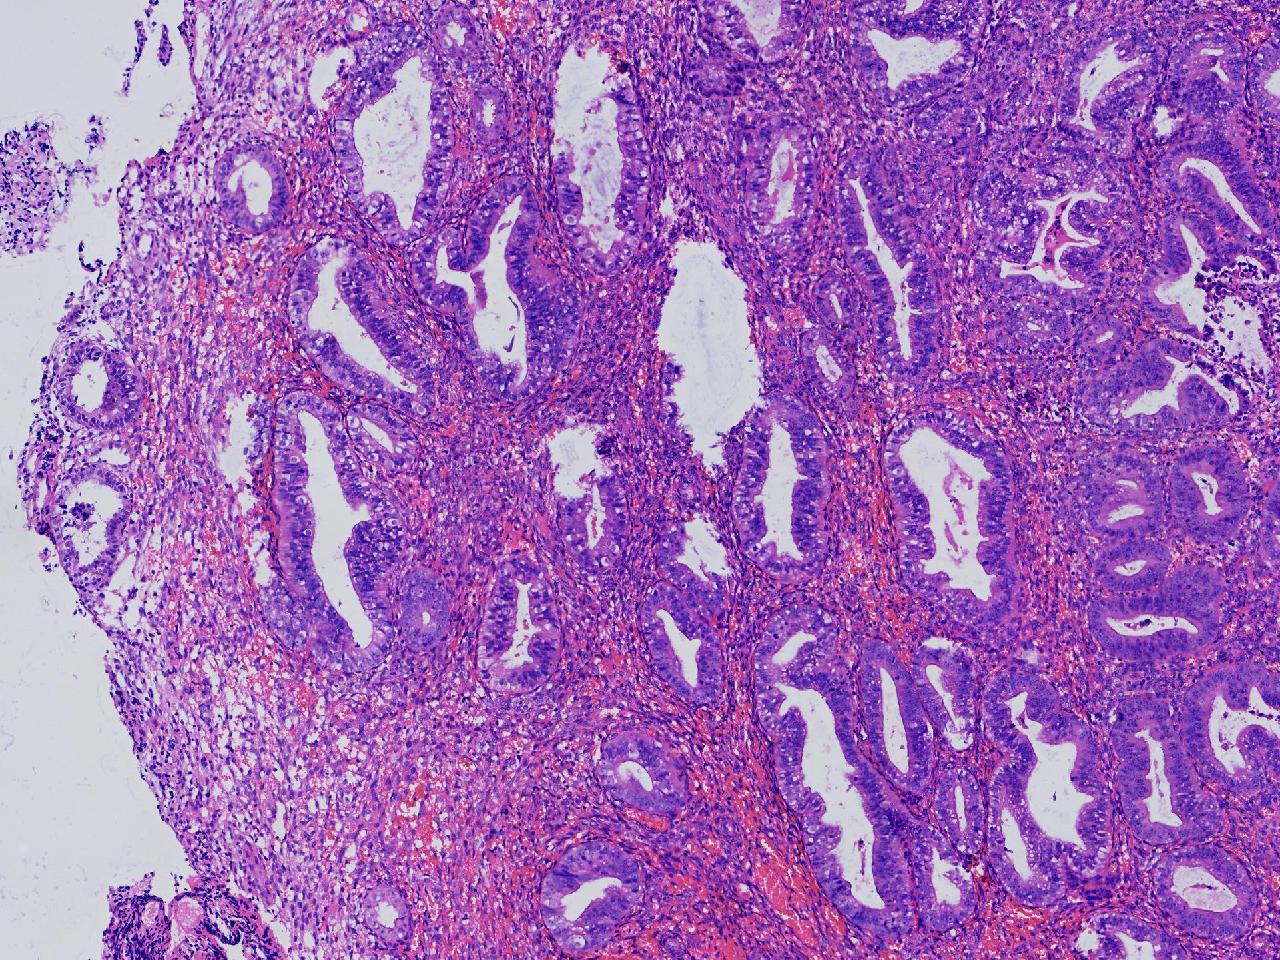

请教诊断.有没有非典?

性别

女

年龄

50岁

女,50岁,彩超示:内膜厚1.3cm。

子宫内膜

灰粉色不整形软组织多块,2X2X1厘米。

无非典型性子宫内膜增生

无非典。